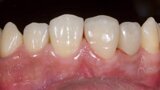

Esthetic Rehabilitation of Maxillary Anterior Teeth: Dr Sanjay Sah